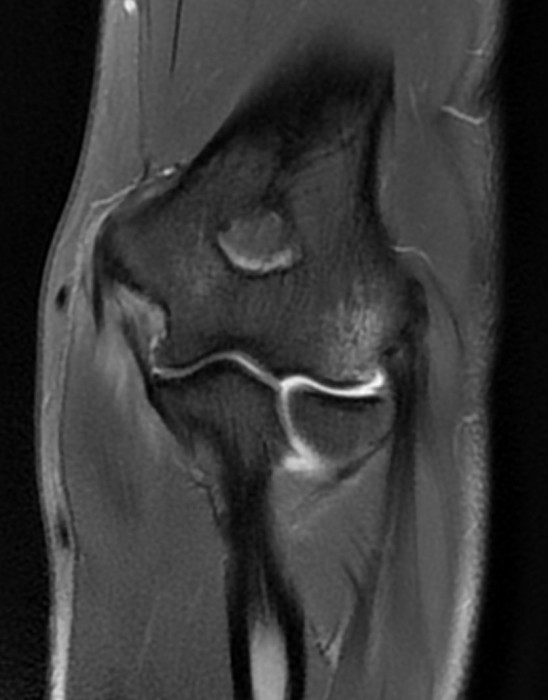

Patient de 44 ans presentant une masse peu sensible de la face palmaire du poignet avec des.

Une anomalie des membres caracterisee par labsence congenitale dun membre a partir du coude. Tumeurs pseudo tumeurs thrombose veineuse ulnaire du poignet irm.